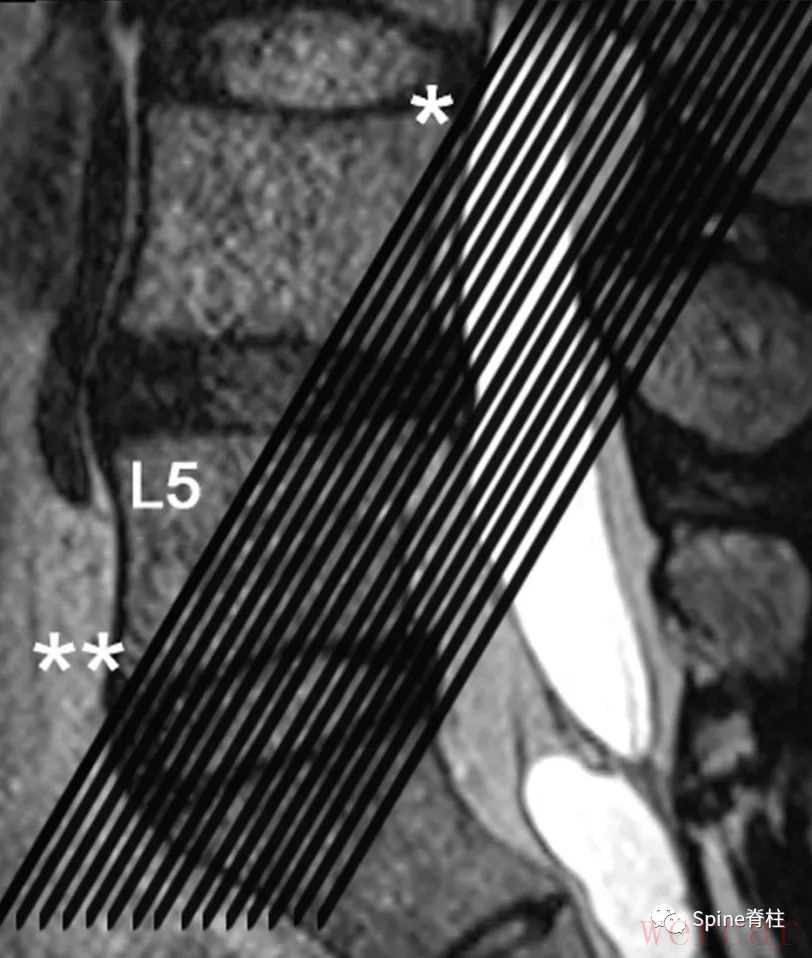

图示:术中证实,右侧L5脊神经(*)在L5横突(**)和骶骨翼(***)之间被压迫。第三种:椎间孔角(FSA)在斜冠状位T2加权的成像(OC-T2WI)

图示:通过T2加权像(T2WI)矢状位显示的斜冠状位T2WI切取的图像。黑线通过L4椎体的上后壁(*)和L5椎体的下前壁(**)。